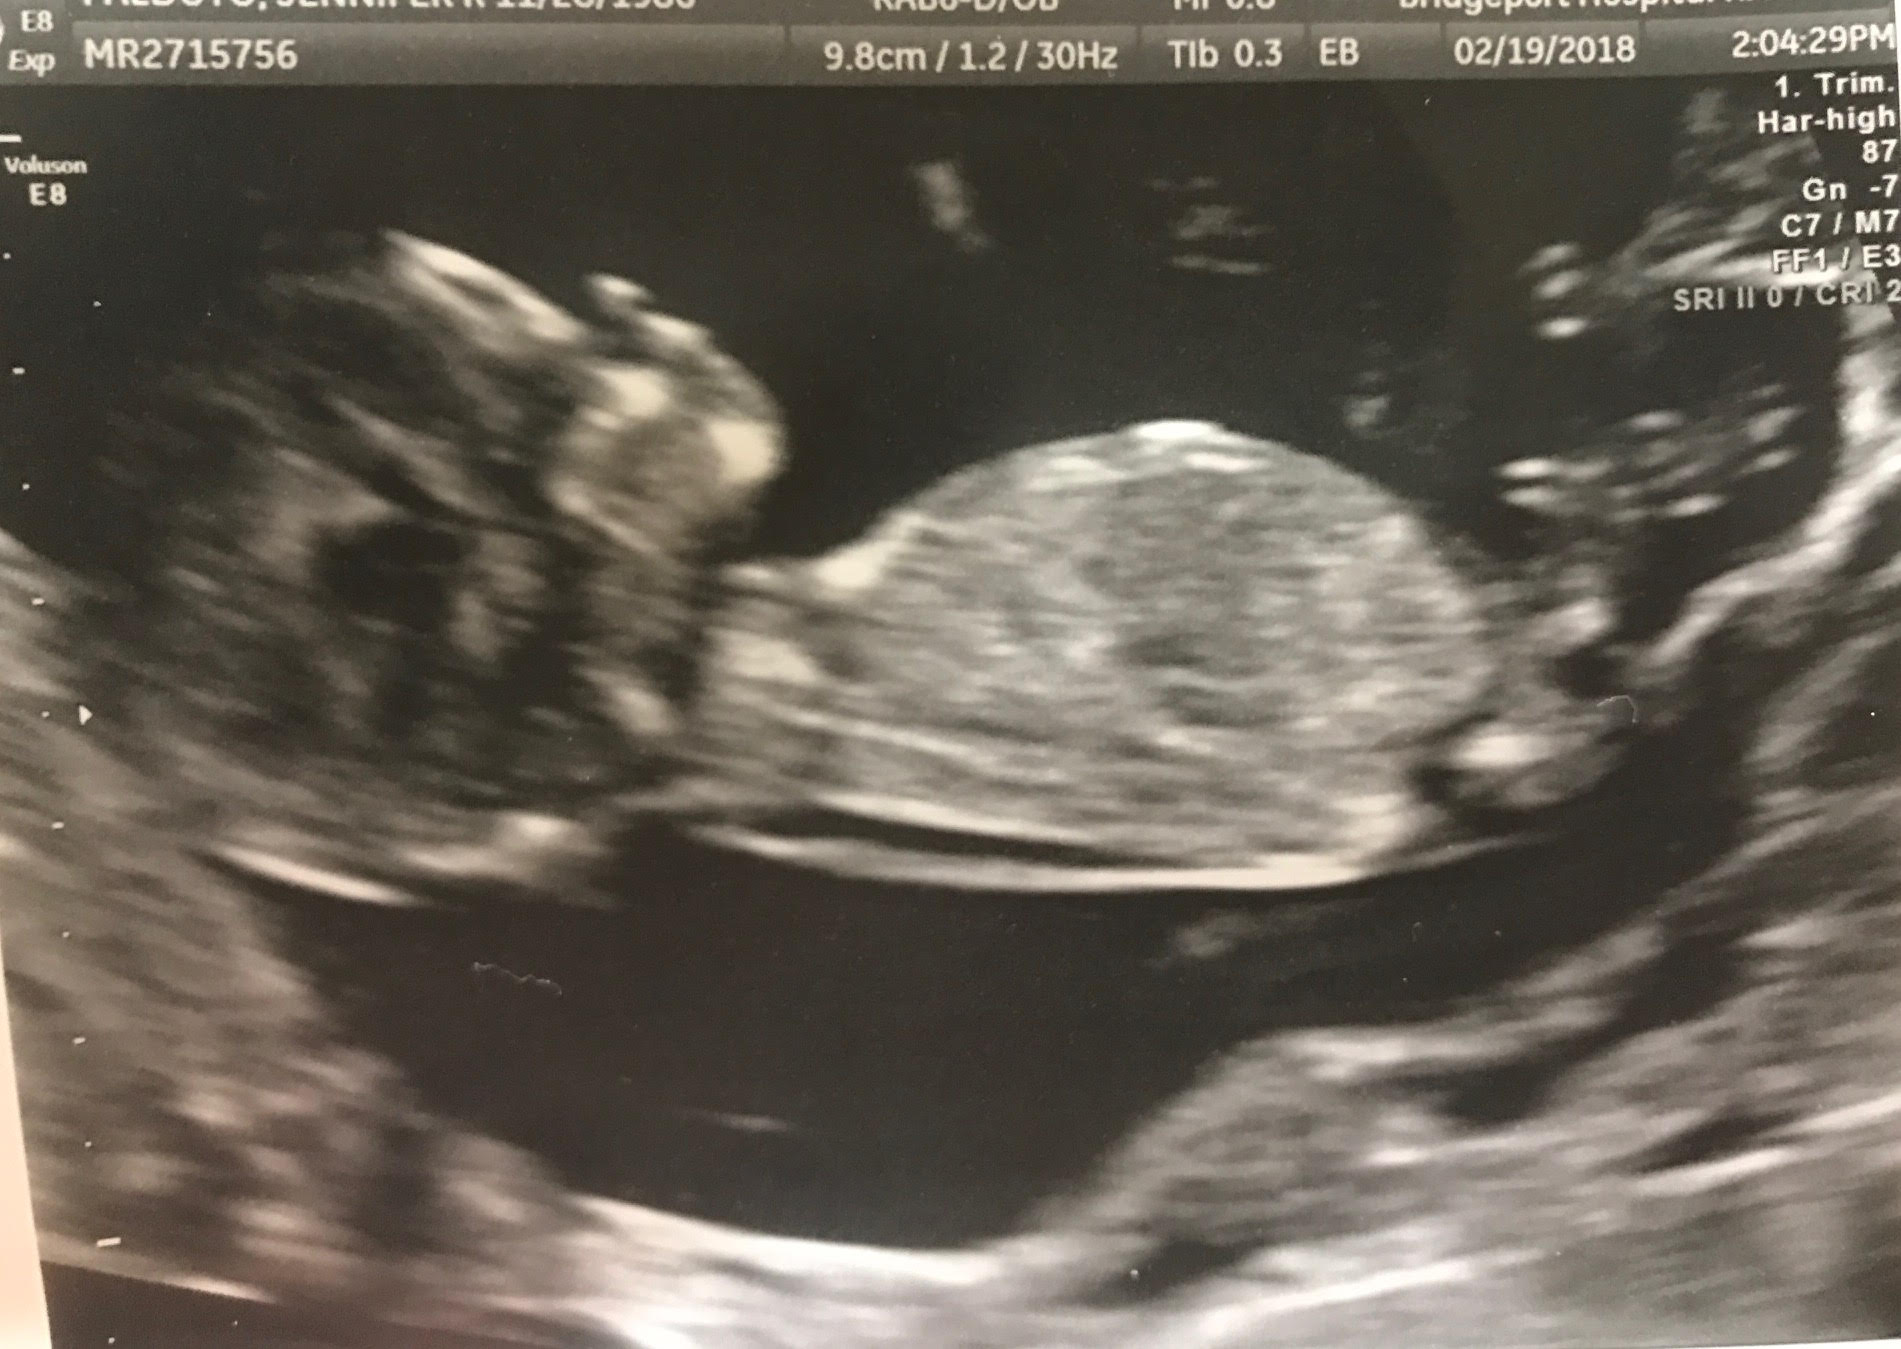

Just had our NT scan at 12 weeks 5 days and would love gender predictions ahead of getting the blood work results back! Have one boy already, swayed pink but with complications so it wasn't a true 100% sway. Thank you ladies in advance! :)Attachment 38839Attachment 38841